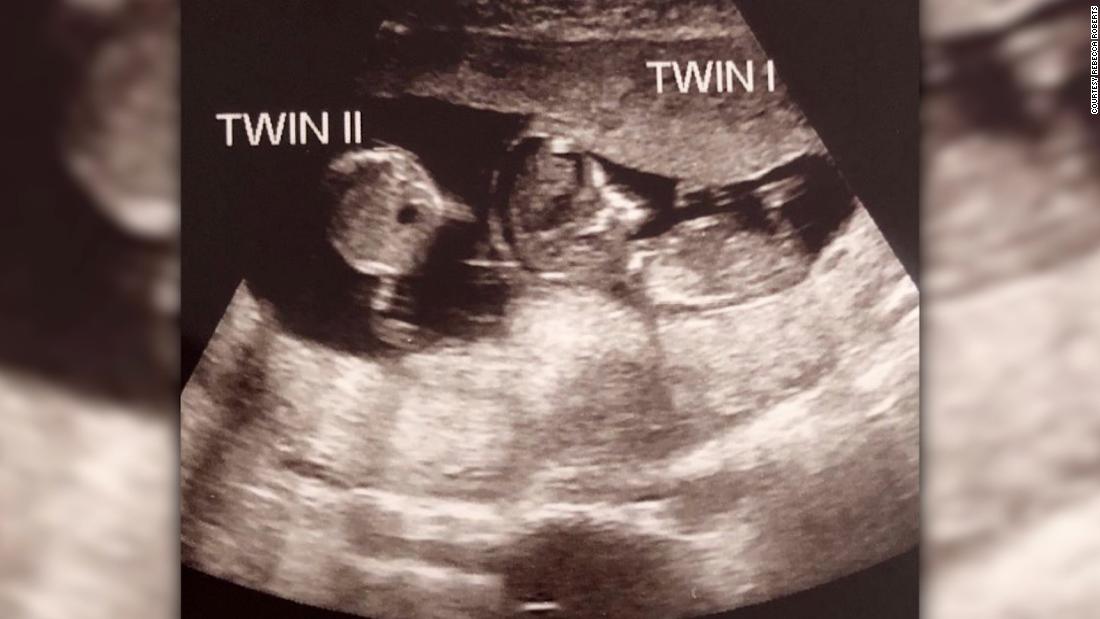

Nhưng sau đó, hình ảnh siêu âm được thực hiện ở tuần thứ 12 cho thấy Noah bất ngờ có một cô em gái nằm chung tử cung mẹ.

Ảnh chụp siêu âm bé Noah có em 3 tuần sau khi được thụ thai. Ảnh: CNN